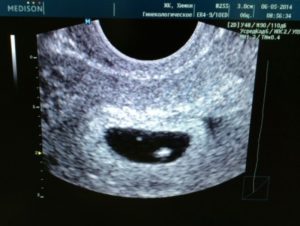

Визуализация плодного яйца чаще всего происходит на сроке беременности около пяти недель, однако его наличие не всегда является залогом развития здоровой беременности.

В середине пятой недели специалист может рассмотреть внутри плодного яйца желточный мешок, который является первым источником питания развивающегося плода. Если на снимке УЗИ становятся различимыми плодное яйцо и желточный мешок, это также не является гарантией здоровой беременности, однако отсутствие последнего может говорить о серьезных патологиях развития эмбриона.